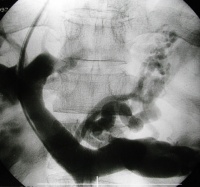

造影显示

造影显示门静脉高压